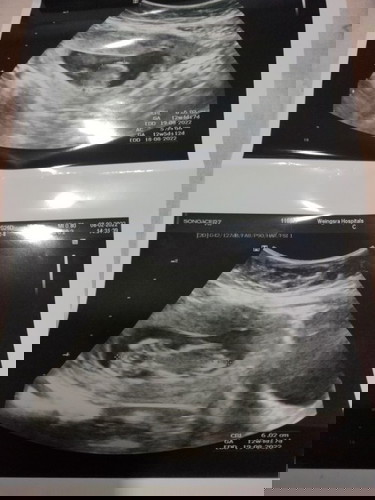

แม่ๆค่ะ #ขอคำแนะนำหน่อยค่ะ #คุณแม่ๆช่วยแนะนำหน่อยค่ะ ไปฝากครรภ์มาค่ะ ตามประจำเดือน น้องอายุครรภ์ 11w5d แต่พอซาวด์ขนาดตัวน้องเท่าอายุ 13w ปกติประจำเดือนแม่มาตรงทุกเดือนนะคะ แต่หมอบอกว่าขอยึดตามผลซาวด์น้อง แบบนี้ไม่เป็นไรใช่ไหมค่ะ #ขอบคุณล่วงหน้านะคะ

เหมือนกันเลยค่ะ ซาวด์ทีไรอายุครรภ์ เพิ่มตลอดเลยค่ะ กำหนดคลอดเลื่อนทุกรอบเลย เราไม่แพ้ท้องเลย แต่น้ำหนักก็ลดนะคะ ตอนนี้เป็นกรดไหลย้อนอีก หมอบอกทานเยอะเกิน ตามใบซาวด์ 13w6d จ้า

ถ้าจะคลอดเองยึดตามประจำเดือนจะดีกว่าค่ะ แต่ถ้าจะผ่า ยึดตามใบซาวได้ค่ะ บ้านนี้ซาวแต่ละครั้งไม่ตรงกันเลยค่ะ เกินเกณฑ์ตลอด

เป็นเหมือนกันค่ะ... ตัวน้องโตกว่าอายุครรภ์ หมอเลยยึดตามผลซาวด์ไปเลยค่ะ กำหนดคลอดก็ยิ่งเร็วขึ้นกว่าเดิม☺️☺️

ไม่เป็นไรค่ะเพราะน้องตัวโตกว่าเกณฑ์คุณหมอเลยจะยึดพัฒนาการน้องจากตรงนั้นเลยค่ะ คงจ้ำม่ำน่าดูเลยนะตัวเล็ก😁

เป็นเหมือนกันค่ะ ของเราถ้านับจาก ปจด มาน้องจะ17 สัปดาห์ แต่ในซาว แค่ 15 สัปดาห์ คุณหมอ นับจากเครื่องซาวค่ะ

เครื่องซาวน์คำนวนจากขนาดน้องค่ะ ถือว่าเป็นเด็กจ้ำม่ำเลยค่ะแม่